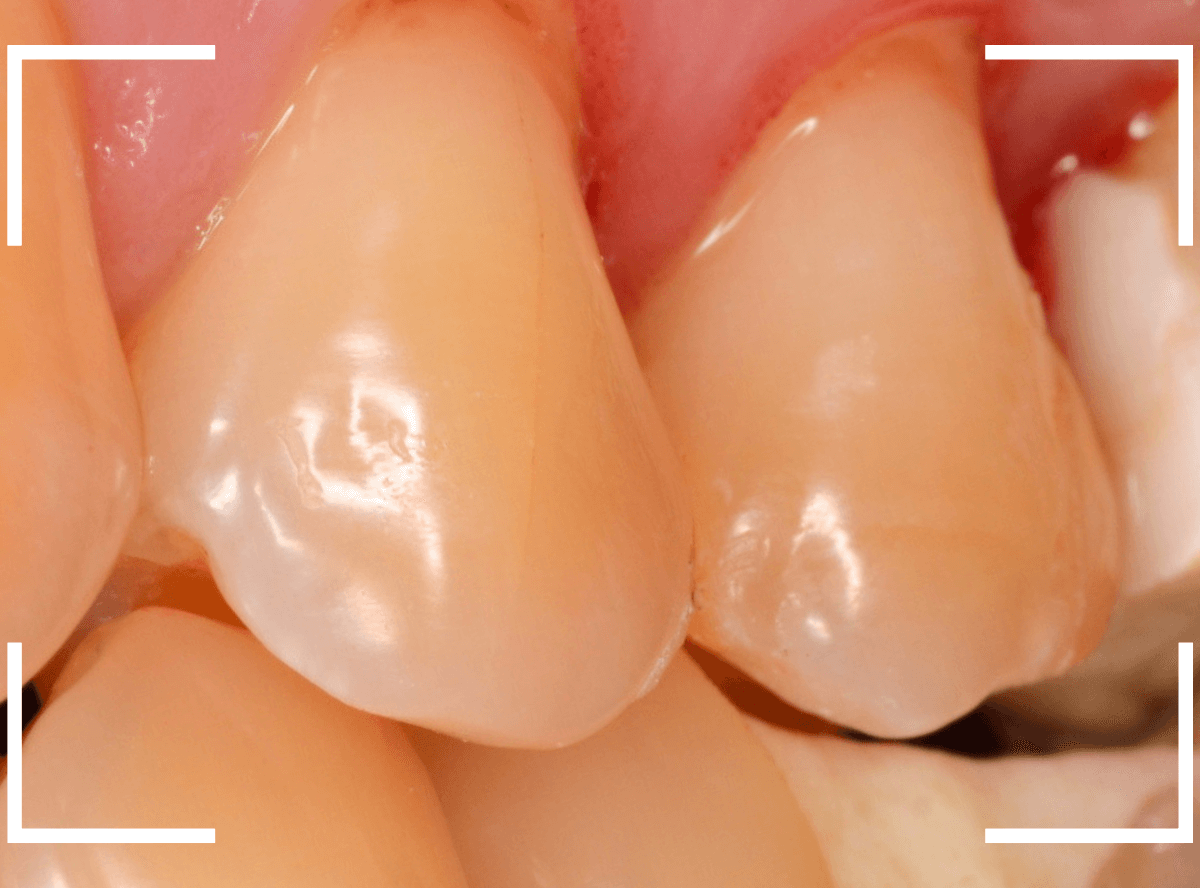

Case.27 乳歯をセラミック・インレー

昔に治療したセラミック・インレーが破折した患者さんのケースです。

破折している部分はわずかですが、セラミックの内面~となりの歯のレジンの中まで虫歯が見られます。

この歯は後続の永久歯のない、乳歯になります。

今後、どの程度保存できるか何とも言えませんが、幸い歯の揺れもなくしっかりしているので、短期間で抜歯が必要になったする事はないとの判断で、セラミック・インレーを除去して再治療する事になりました。

虫歯と歯のトリミング処置したところです。

奥歯をレジンでつめ直し、手前の乳歯はE-max・インレーで再製する事になりました。